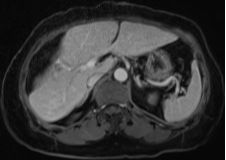

結(jié)腸腫瘤是指發(fā)生在結(jié)腸部位的腫瘤,可分為良性和惡性,結(jié)腸腫瘤早期癥狀不明顯,隨著病情發(fā)展,可能出現(xiàn)腹痛、便血、腸梗阻等癥狀,治療方法包括手術(shù)、化療、放療等,具體治療方案需根據(jù)患者的具體情況制定。

3、結(jié)腸腫瘤的治療:包括手術(shù)、化療、放療等,具體治療方案需根據(jù)患者的具體情況制定。